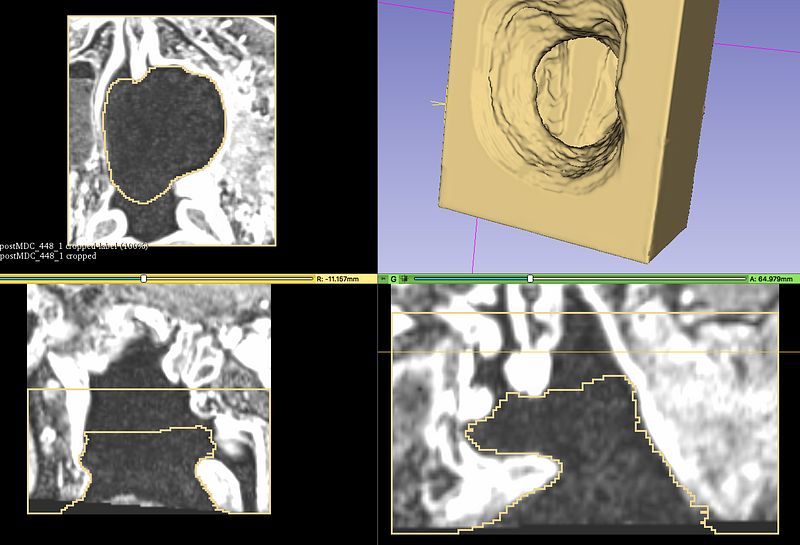

This work aims to define an accessible workflow for the design and manufacturing of maxillofacial obturator prostheses from DICOM files for patients with reduced mobility of the oral cavity. Starting from a case study, the STL file of the injured area was generated to develop the parametric 3D model of the mold. The mold was then manufactured with a low-cost 3D printer, and the palatal obturator was obtained by silicone casting. The patient has improved his quality of life by recovering some vital functions. This workflow may overcome conventional processes, leading to develop new patient-specific prostheses in critical situations. 1